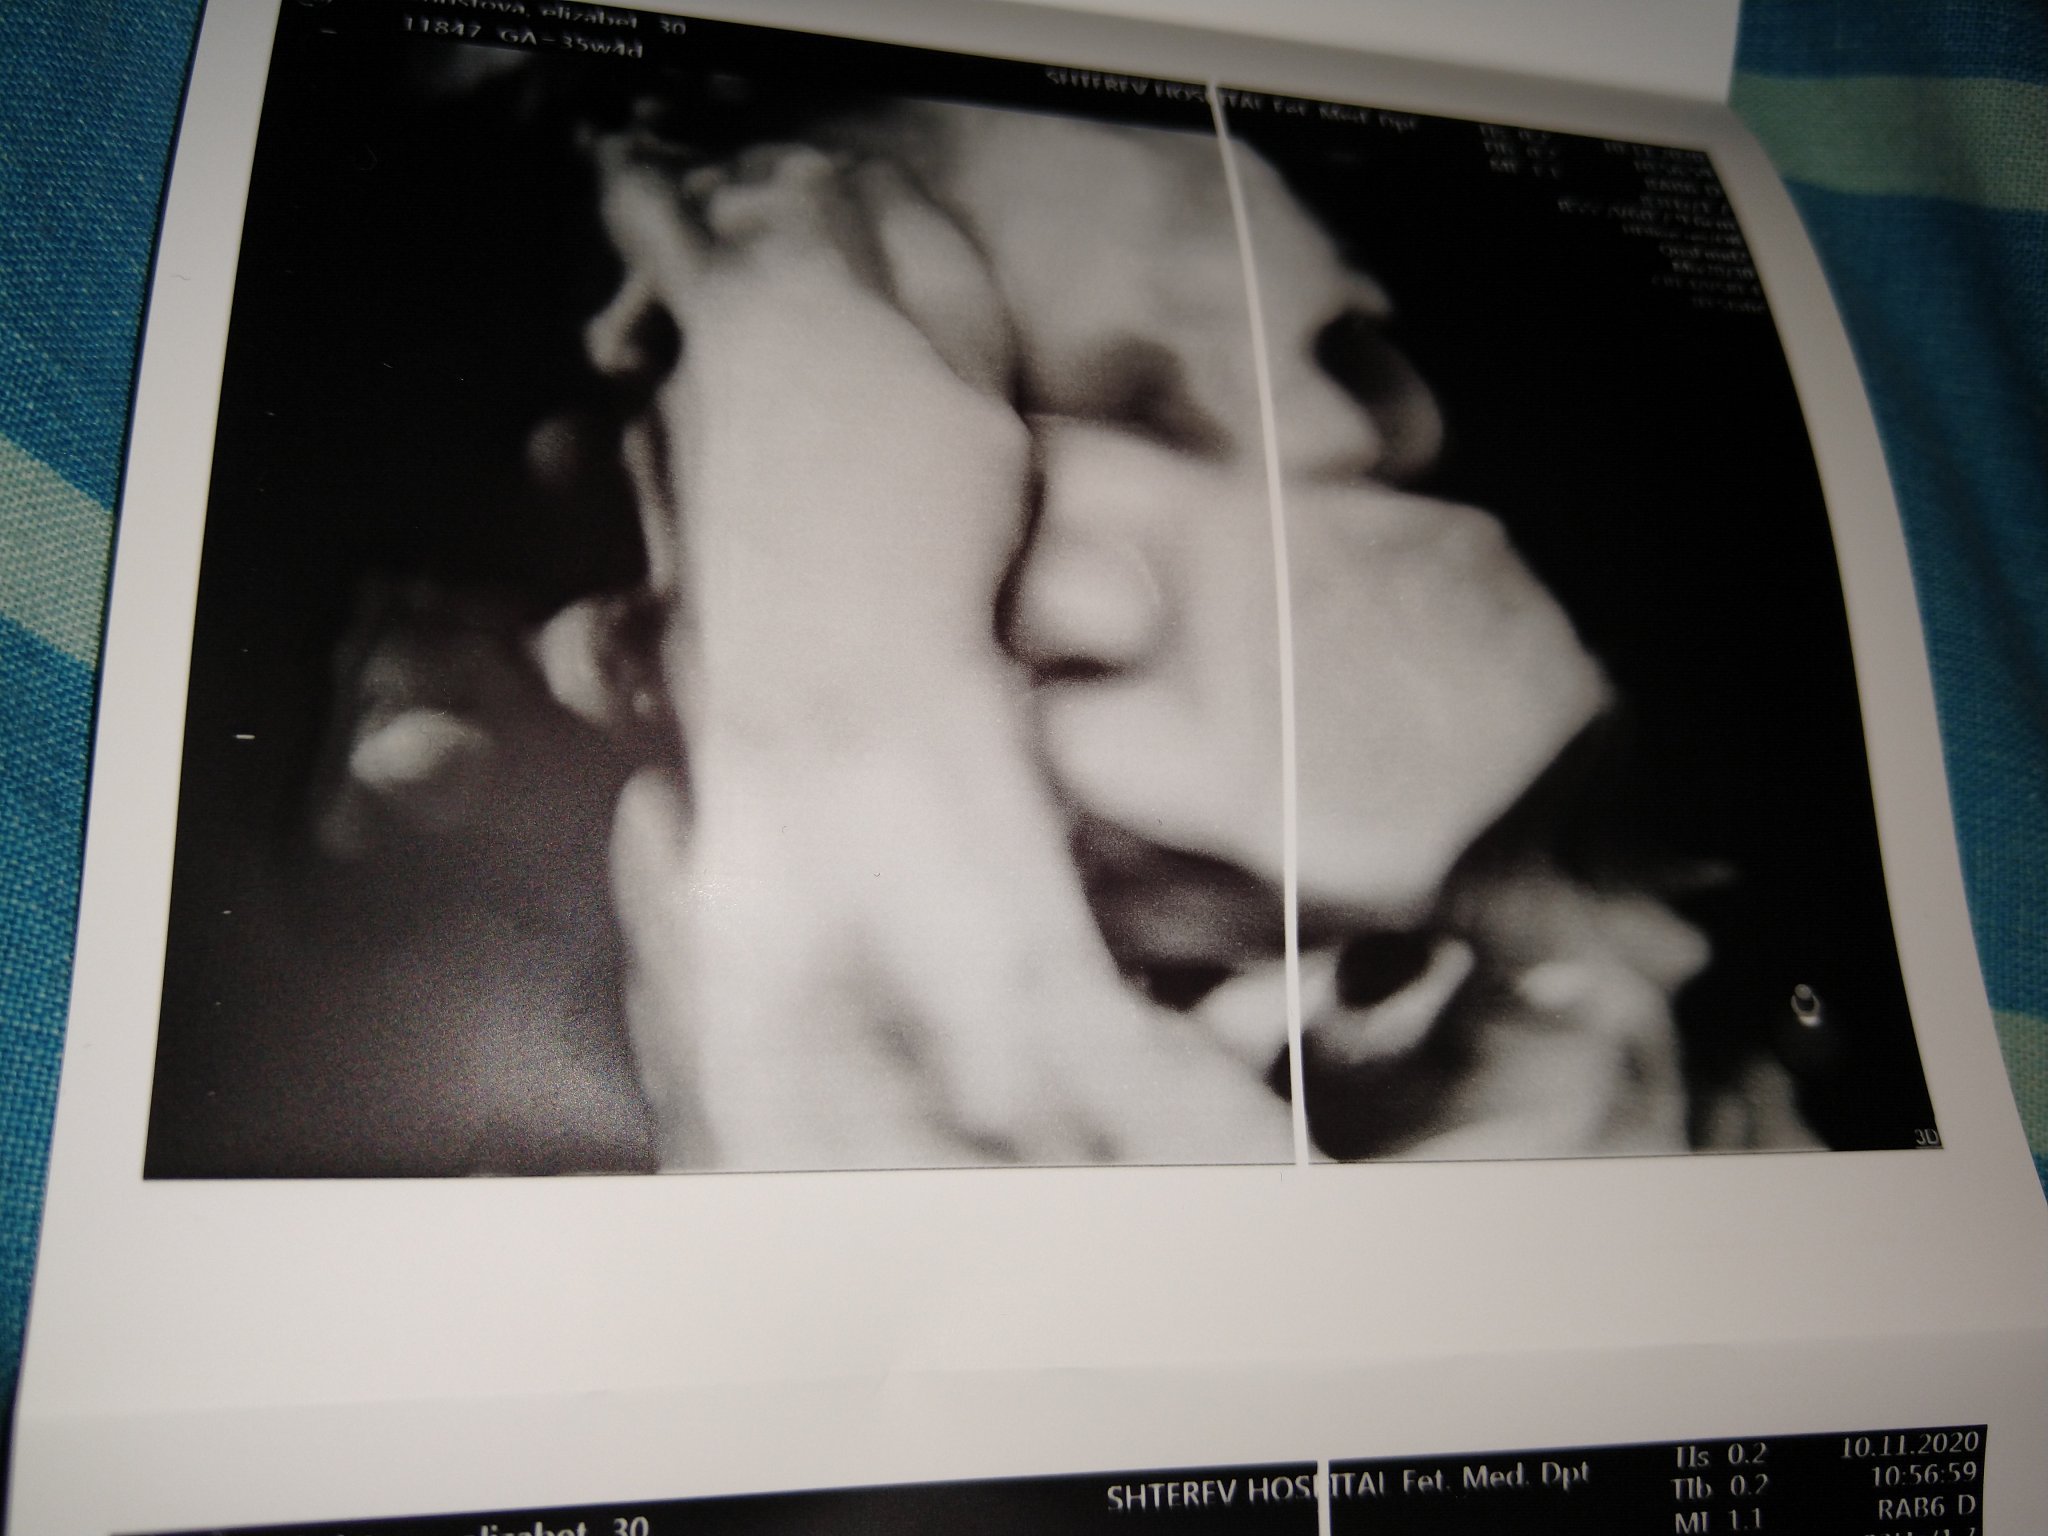

Моя сраежливко от днес, нямам нито една снимка, на която да не се е скрил.